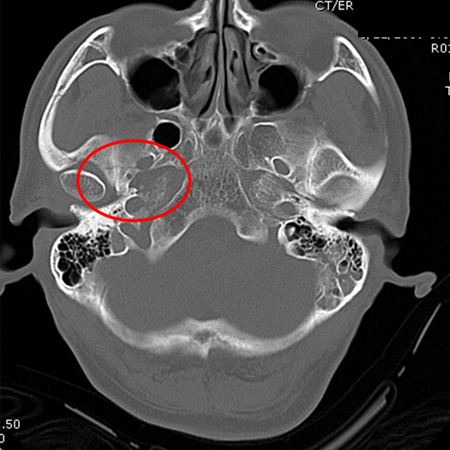

[Figure caption and citation for the preceding image starts]: Occipital fracture extending to foramen magnum: risk of brainstem compression by haematoma [Citation ends].